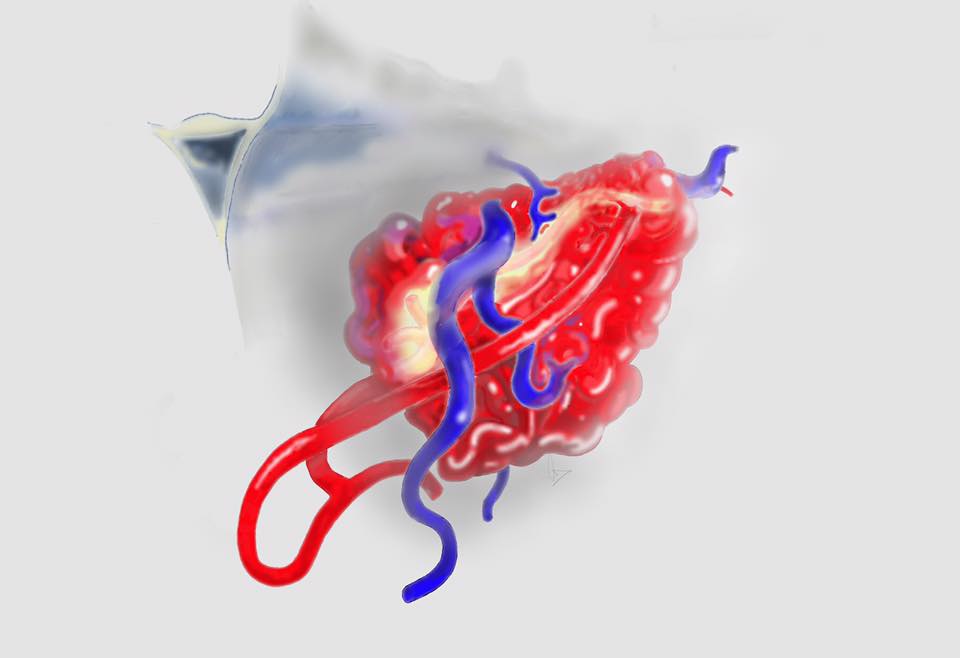

病人….被另一名曾經嚴重腦出血性中風(腦動脈瘤破裂以致嚴重的蜘蛛綱膜下腔出血及曾經瞳孔放大和深度昏迷…其後完全康復)的病人介紹…..帶MRI 底片到我診所尋求第二醫療諮詢….. 其時心情亦愉快…….直到….看了MRI 影像後…..我告訴她真正的MRI檢查結果……她的左前腦額葉上….有一個3cm大的腦動靜脈畸形血管瘤(AVM).. ….亦有最近出過血的跡象…可能是她失去意識和腦癇症的原因。

兩天後….在私家醫院為她做診斷式的動態腦血管造影來確定䐉血液的流動模式後,再進行了4 小時的顯微鏡手術….AVM的計時炸彈完全切除……..在AVM旁邊的腦部亦能看到血鐵黃素的舊有殘留血液。手術後兩天出院。